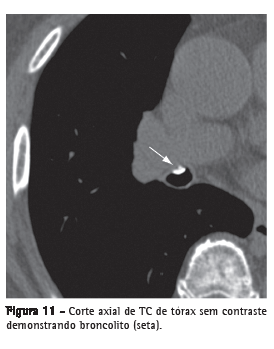

Broncolito

Linfonodo peribrônquico calcificado que erode para o interior do brônquio adjacente, geralmente secundário a infecções por Histoplasma sp. ou Mycobacterium ­tuberculosis. Na TC, é identificado como um pequeno foco de calcificação dentro da ou adjacente à via aérea, mais frequentemente no brônquio do lobo médio (Figura 11). Distalmente, pode existir impacção de secreções, bronquiectasias ou atelectasia.(24,25)